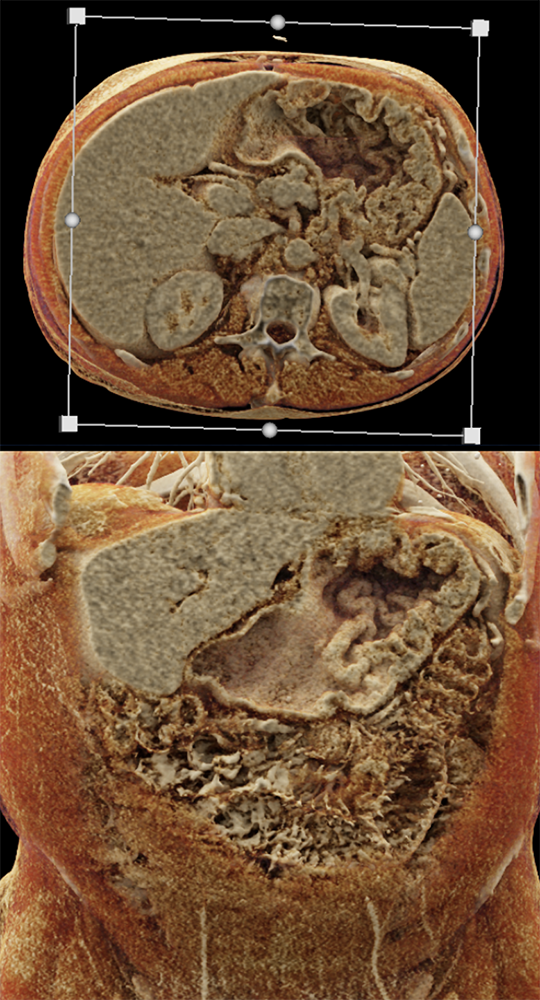

Watermelon stomach (WMS), or gastric antral vascular ectasia (GAVE) ![]() |

“Gastric antral vascular ectasia primanily affects women (9:1 female-to-male ratio) aged 56-76 years, and is associated with liver cirrhosis (37%) and achlorhydnia (35%). The usual symptoms are iron-deficiency anemia and melena due to chronic gastrointestinal bleeding from the dilated, superficial, and easily traumatized vessels. Antrectomy is curative, but endoscopic treatment with heat probes or lasers has shown promise.” Gastric antral vascular ectasia ("watermelon stomach"): radiologic findings. Urban BA, Jones B, Fishman EK, Kern SE, Ravich WJ. Radiology. 1991 Feb;178(2):517-8. |

“In our patient, the findings of prominent mucosal folds extending from the pylonic channel on upper gastrointestinal series and the thickened antral wall on CT scans correlate well with the known pathologic appearance of gastnic antral vascular ectasia. Histologically, antral thickening results from a combination of foveolar and fibromuscular hyperplasia. Grossly, the antral fold prominence appears to result from bunching of the mucosa in the thickened, hypercontractile antrum.” Gastric antral vascular ectasia ("watermelon stomach"): radiologic findings. Urban BA, Jones B, Fishman EK, Kern SE, Ravich WJ. Radiology. 1991 Feb;178(2):517-8. |

“Watermelon stomach (WMS), or gastric antral vascular ectasia, is an uncommon but clinically important cause of chronic occult or overt gastrointestinal (GI) blood loss. Patients typically present with symptomatic anemia and hemoccult positive stools. Although the diagnosis is based primarily on the typical endoscopic appearance, the lesion may be overlooked on initial evaluation or interpreted as "gastritis." Gastric biopsy may be helpful in confirming the diagnosis by showing vascular ectasia, typically without inflammation. WMS is idiopathic but is often associated with autoimmune diseases or cirrhosis of the liver. The majority of patients with classic WMS are elderly and female.” |

“Gastric antral vascular ectasia (GAVE) is a rare entity with unique endoscopic appearance described as "watermelon stomach." It has been associated with systemic sclerosis but the pathophysiological changes leading to GAVE have not been explained and still remain uncertain.” Gastric Antral Vascular Ectasia in Systemic Sclerosis: Current Concepts. Parrado RH et al. Int J Rheumatol. 2015;2015:762546. |